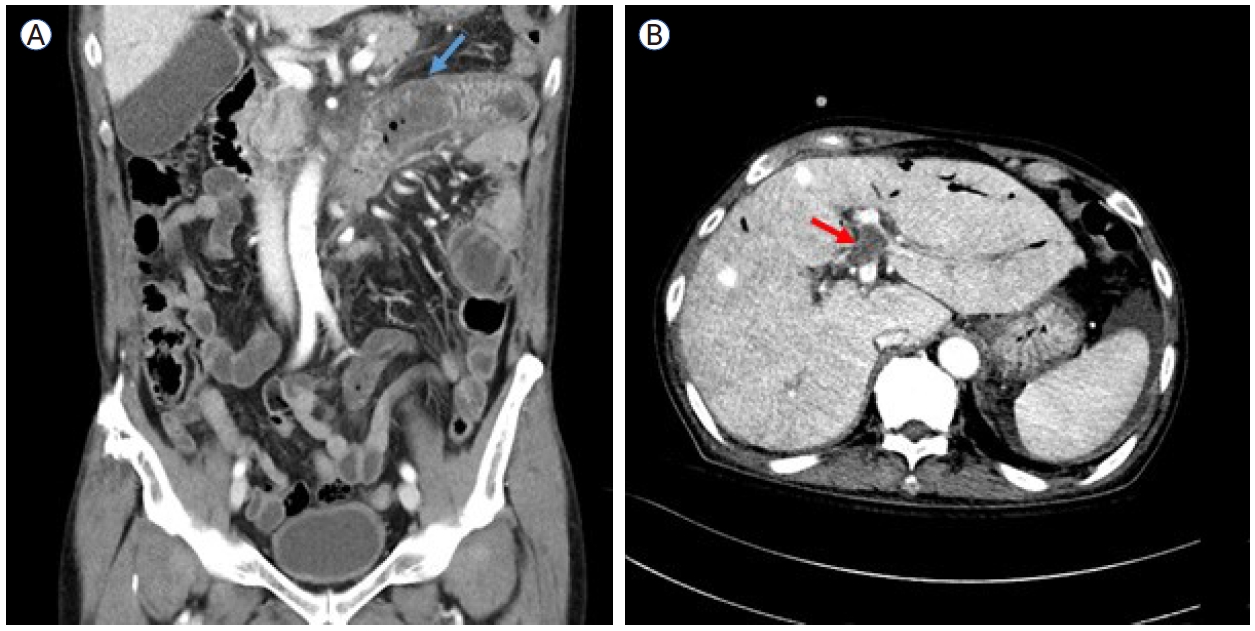

On August 19, 2024, the patient presented with abdominal pain and oral mucosal swelling. CT findings, together with dental examination results, suggested the development of ischemic enterocolitis (Fig. 2A) and necrotizing gingivitis, likely secondary to occult thrombosis. Progressive anemia (hemoglobin, 7.0 g/dL) was also noted, accompanied by gross hematuria and an elevated LDH level (787 U/L), consistent with IVH. Empirical antibiotics and intravenous steroid pulse therapy (mPD, 1 mg/kg) were initiated, resulting in symptom relief and stabilization of laboratory parameters. However, during steroid tapering, all symptoms and signs recurred, necessitating an increase in the steroid dosage. On September 19, the patient again reported abdominal pain with right upper quadrant tenderness and abdominal distension. A CT scan revealed a new non-malignant thrombus in the left portal vein (Fig. 2B) and the presence of ascites, which was further evaluated by a serum-ascites albumin gradient of 1.8 g/dL, indicating portal hypertension. On October 17, the patient developed epididymo-orchitis with a strong suspicion of ischemic infarction. Subsequently, prolonged steroid exposure led to the development of gastric and duodenal ulcers complicated by gastrointestinal bleeding, which required hemoclipping on three occasions.

Figure 2.

Computed tomography images of the patient’s abdomen. (A) Short segmental wall thickening in the proximal jejunum and the third and fourth portions of the duodenum (red arrow), suggestive of bowel ischemia secondary to occult thrombosis. (B) A newly developed thrombus in the umbilical segment of the left portal vein (blue arrow), accompanied by ascites.